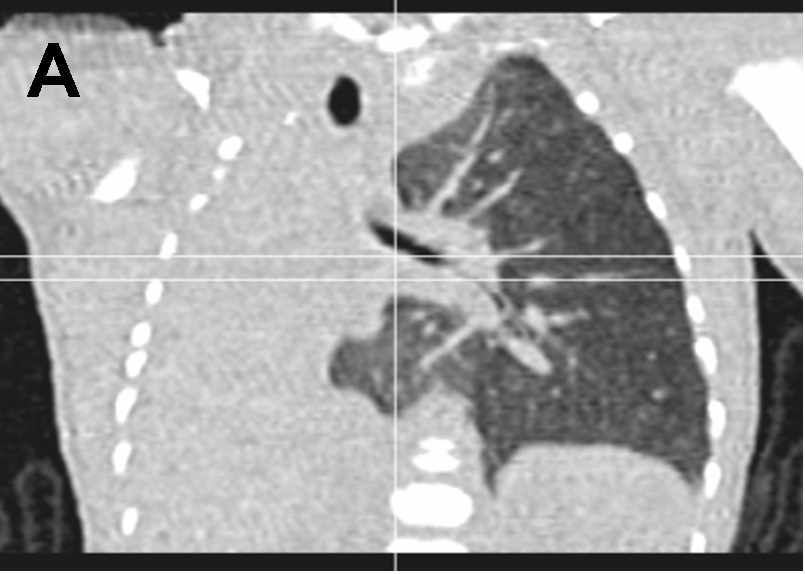

Recién nacido de 33 semanas y 1500 g de peso que ingresa por prematuridad y distrés respiratorio. Embarazo controlado irregularmente. Apgar 6/8. En la exploración al nacimiento se detecta tiraje sub- e intercostal leve, hipoventilación en hemitórax derecho, tonos cardiacos desplazados ipsilateralmente y abdomen excavado. Precisa ventilación no invasiva con presión positiva continua de la vía aérea (CPAP) durante las primeras horas de vida, quedando posteriormente en respiración espontánea. Se realiza una radiografía de tórax (Figura 1).